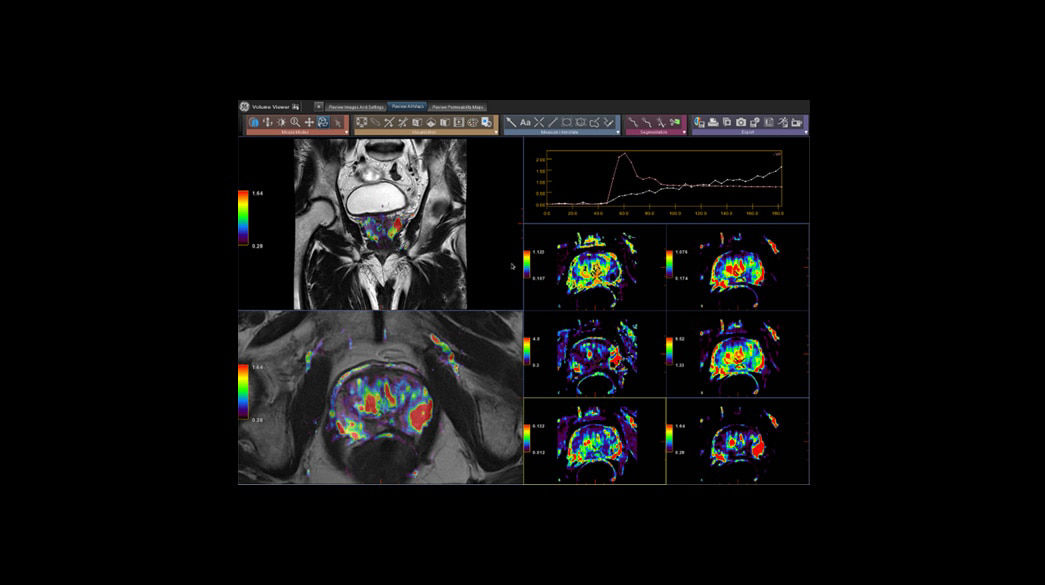

Quantifiable

Provides quantitative and actionable information

Consistent

Motion and distortion-reduced scans with high-resolution and contrast